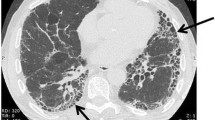

Both clinicians and scientists intuitively approach fibrosis as a pathological process; however, it can be argued that fibrosis serves an adaptive host response function [20]. Accordingly, fibrosis may be viewed as a physiological response conserved through evolution for survival after tissue injury, even at the cost of a loss in organ structure/function. This ‘trade-off’ would be predicted to select fibrotic repair over ‘perfect’ organ regeneration in environments of limited bioenergetic resources. Progressive fibrosis may occur when the normal bidirectional signalling between the epithelium and the mesenchyme (fibroblasts) that coordinates repair becomes aberrant in the context of chronic injury and aging. This aberrant signalling may result from several factors, such as elevated oxidative stress, impaired fibrinolysis, and alterations in cytokines, chemokines, growth factors and eicosanoids [21]. Ultimately, the causes of pathological fibrosis likely involve impaired ability to clear antigens, autoimmunity, impaired regeneration and aberrant activation of developmental or wound-healing genes [20]. In the context of aging, senescence of both the epithelium and the mesenchyme may be predicted to give rise to cell phenotypes and fates that are characteristic of non-resolving fibrosis (Fig. 1). Consequently, the putative therapeutic targets are myriad and provide an opportunity for a multipronged approach to intervene along a spectrum, from halting the progression of fibrosis to reversing remodelling in order to achieve normal organ structure and function.

Proposed mechanisms for the predisposition to fibrosis with aging. Aging may result in ‘immunosenescence’, which results in impaired antigen clearance and autoimmunity; additionally, senescence of epithelial cells and fibroblasts results in impaired regeneration and aberrant recapitulation of developmental genes. These processes may perpetuate epithelial injury/apoptosis and fibroblast activation, which result in failed re-epithelialization, fibroblast persistence and progressive fibrosis